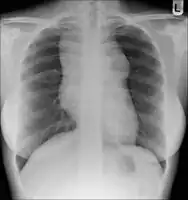

• Lymphadenopathy: the most common symptom of Hodgkin is the painless enlargement of one or more lymph nodes.[14] The nodes may also feel rubbery and swollen when examined. The nodes of the neck and shoulders (cervical and supraclavicular) are most frequently involved (80–90% of the time, on average).[14] The lymph nodes of the chest are often affected, and these may be noticed on a chest radiograph.[14]

After Hodgkin lymphoma is diagnosed, a person will be staged: that is, they will undergo a series of tests and procedures that will determine what areas of the body are affected. These procedures may include documentation of their histology, a physical examination, blood tests, chest X-ray radiographs, computed tomography (CT)/Positron emission tomography (PET)/magnetic resonance imaging (MRI) scans of the chest, abdomen and pelvis, and usually a bone marrow biopsy. Positron emission tomography (PET) scan is now used instead of the gallium scan for staging. On the PET scan, sites involved with lymphoma light up very brightly enabling accurate and reproducible imaging.[29] In the past, a lymphangiogram or surgical laparotomy (which involves opening the abdominal cavity and visually inspecting for tumors) were performed. Lymphangiograms or laparotomies are very rarely performed, having been supplanted by improvements in imaging with the CT scan and PET scan.